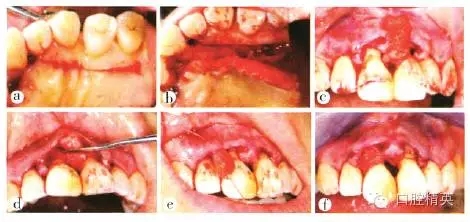

(1)切口:在必蘭(鹽酸阿替卡因腎上腺素注射液,1.7 mL)局麻下,于21 12唇側(cè)做溝內(nèi)切口,腭側(cè)做半月形切口,保留齦乳頭,并將齦乳頭自腭側(cè)完整翻至唇側(cè),徹底清創(chuàng),術(shù)中測量11根方接觸點與骨嵴頂距離為10 mm(圖4~5)。

a 2112唇側(cè)做溝內(nèi)切口;b 腭側(cè)做半月形切口,保留齦乳頭;c 將齦乳頭自腭側(cè)完整翻至唇側(cè);d 切口腭側(cè)觀

圖5 牙周膜齦手術(shù)切口

(2)軟組織移植:采用牙周顯微器械,自23456腭側(cè)齦緣根方3 mm相應(yīng)處,沿牙列方向水平切口并近遠中向延展至約25 mm長,制備長25 mm、寬10 mm的帶蒂結(jié)締組織瓣,蒂部與噎腭側(cè)軟組織相連,自其游離端截取長約10 mm、寬10 mm的游離結(jié)締組織備用。通過11牙間隙將帶蒂組織瓣自腭側(cè)翻卷至唇側(cè),并固定于唇側(cè)齦瓣根方組織面,以增厚齦乳頭。將截取的游離結(jié)締組織固定于21間齦乳頭下方組織面(圖6)。用渦輪鉆處理11根面,去除污染層,用生理鹽水沖洗。

a 自23456腭側(cè)齦緣根方3 mm相應(yīng)處做水平切口;b 制備帶蒂結(jié)締組織瓣,長25 mm、寬10mm,蒂部與幢腭側(cè)軟組織相連;c 通過11牙間隙將帶蒂組織瓣自腭側(cè)翻卷至唇側(cè);d 將帶蒂組織瓣同定于唇側(cè)齦瓣組織面.增厚齦乳頭;e 將截取的游離結(jié)締組織瓣置于21之間;f 固定組織瓣于21間齦乳頭下方組織面

圖6 軟組織移植

(3)縫合:松弛211唇側(cè)齦瓣,冠向懸吊,并以流動樹脂固定線結(jié)于1 1冠中1/3處。21 12齦乳頭處間斷縫合,23456腭側(cè)供區(qū)鎖扣式縫合(圖7)。術(shù)后上頜戴入壓膜式牙合墊,保護供區(qū)創(chuàng)口,壓迫止血。

a松弛211唇側(cè)齦瓣,冠向懸吊并以流動樹脂固定線結(jié)于11冠中1/3處,2112齦乳頭間斷縫合;b腭側(cè)觀;c供區(qū)鎖扣式縫合

圖7 術(shù)后縫合